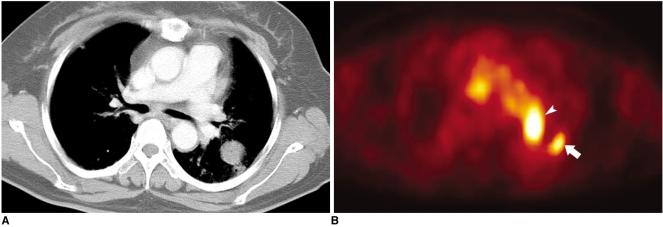

Fluorodeoxyglucose (FDG)-positron emission tomography (PET) is being used more and more to differentiate benign from malignant focal lesions and it has been shown to be more efficacious than conventional chest computed tomography (CT). However, FDG is not a cancer-specific agent, and false positive findings in benign diseases have been reported. Infectious diseases (mycobacterial, fungal, bacterial infection), sarcoidosis, radiation pneumonitis and post-operative surgical conditions have shown intense uptake on PET scan. On the other hand, tumors with low glycolytic activity such as adenomas, bronchioloalveolar carcinomas, carcinoid tumors, low grade lymphomas and small sized tumors have revealed false negative findings on PET scan. Furthermore, in diseases located near the physiologic uptake sites (heart, bladder, kidney, and liver), FDG-PET should be complemented with other imaging modalities to confirm results and to minimize false negative findings. Familiarity with these false positive and negative findings will help radiologists interpret PET scans more accurately and also will help to determine the significance of the findings. In this review, we illustrate false positive and negative findings of PET scan in a variety of diseases.